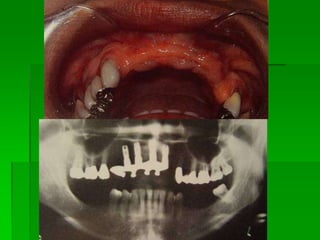

Avaliação Clínica no Momento da Instalação do ImplanteAparelhos especiais Osstell (mede por freqüência e ressonância)Avaliação Clínica (estabilidade)Torquímetro (mínimo 45 Newtons)Avaliação   radiográfica   ( durante   a instalação,  mede  a  distância   entre implantes e estruturas adjacentes)

Avaliação Clínica Após Período de Osseointegração Imobilidade ClínicaAssintomáticoAusência de imagem radiolúcida peri-implantarAusência de neuropatiaPerda óssea vertical inferior a 1,0 mm após o primeiro ano em  função, e  de   0,1 mm nos anos seguintes

Paciente EdentadoAnálise radiográficaPanorâmicaPerfilTCAnálise de ModelosAnálise Clínica

Tomografia computadorizada